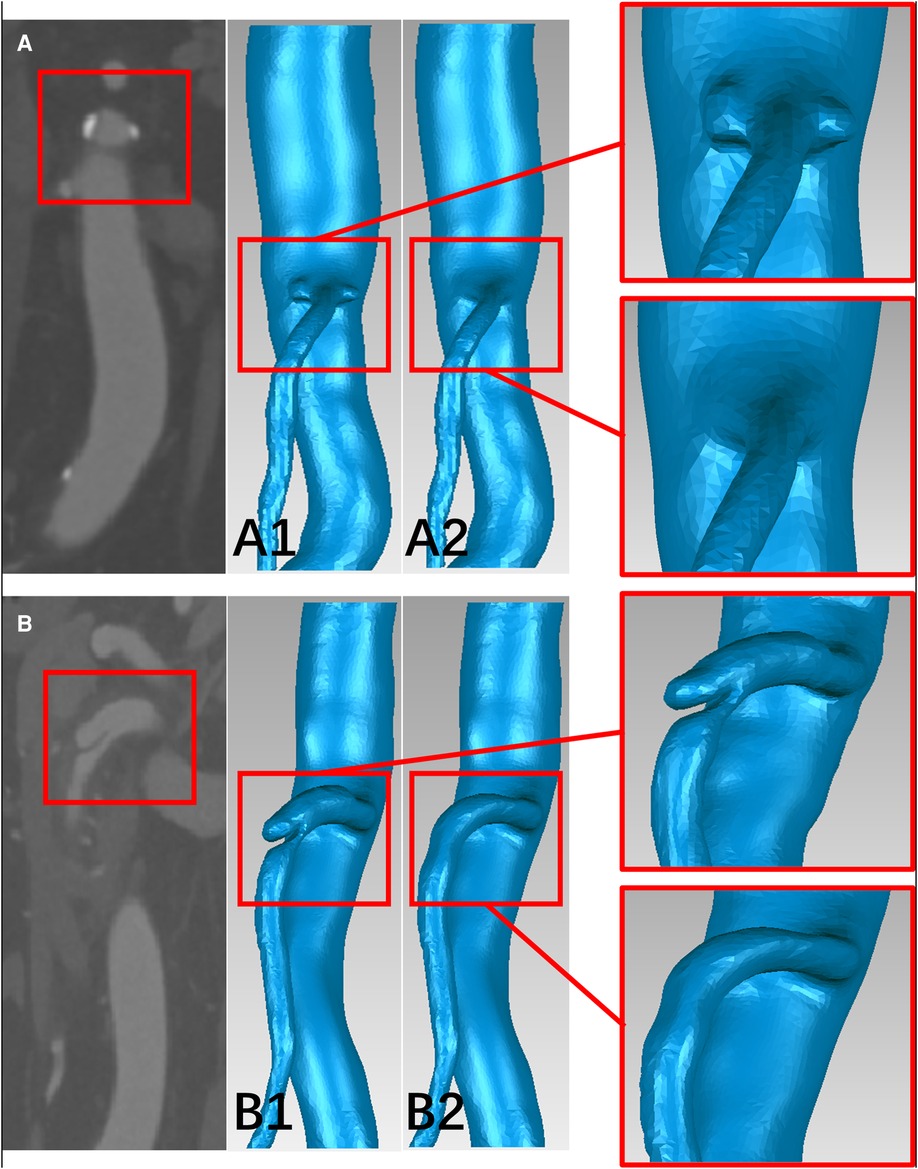

The 3D surface of the SMA was abstracted from the CTA data using Mimics Research 19.0 (Materialise HQ, Louvain, Belgium). The models were then modified based on data from 60 patients, with SMAD (n = 30) and SMAS (n = 30), thirty-one SMAD patients who lack thin-slice CTA data or have poor image quality were excluded in the CFD analysis. At the same time, thirty SMAS patients meeting the including criteria were randomly included. For each model, dissections or plaques were removed and the main morphology features of the SMA trunk were retained to simulate the hemodynamic conditions in the SMA before the onset of SMAD or SMAS; this procedure was performed using Geomagic Wrap 2017 (Geomagic Studio, Raindrop, Research Triangle Park, NC, USA) and SolidWorks 2017 (Dassault Systemes SE, Paris, France) (Figure 2). The SMA models was divided into three segments: the root, the curved segment, and the distal segment. The root was identified as the region 0 to 5 mm away from the SMA ostium; the curved segment was identified as the region 15 to 30 mm away from the ostium; and the distal segment was identified as the region 40 to 55 cm away from the ostium.

Figure 2. The schematic diagram of the progress of removing the plaques and dissections from the models. (A,B) CTA image of plaques at the root of the superior mesenteric artery (SMA) and dissection at the curved segment of the SMA. (A1,B1) The superior mesenteric atherosclerotic stenosis (SMAS) and superior mesenteric artery dissection (SMAD) models before repairing. (A2,B2) the SMA models before the onset of SMAS and SMAD.